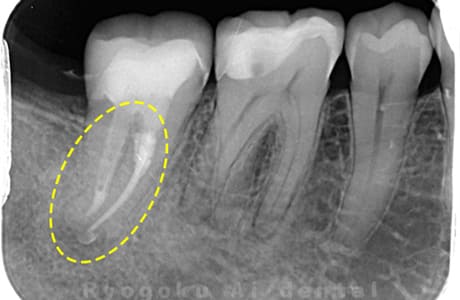

Case03

- 原因

- 急性化膿性根尖性歯周炎

- 治療期間

- 2ヶ月

- 治療内容

- マイクロエンド

- 治療費用

- 121,000円

黙っていても痛みが出るとのことで来院した患者様です。本治療は症状もあるため、抜髄治療をマイクロエンドで行いました。

<リスク・副作用>

術後は痛み、腫れ、痺れなどの副作用が生じる場合があります。症状が再発する可能性があります。